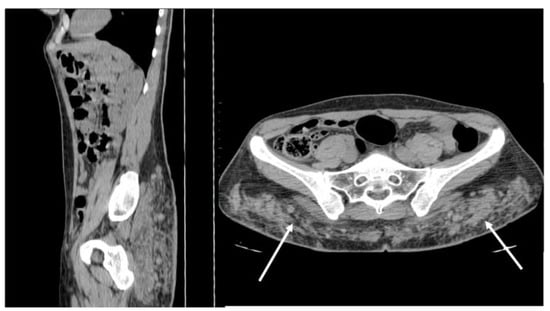

Figure 2. CT appearance of necrotizing fasciitis in a 58-year-old woman with a recent left lower limb open wound who arrived at the ER in septic shock. Arterial phase axial CT scan reveals the presence of free air in the fascial planes of the left lateral and posterior abdominal wall, with fascial thickening and lack of muscular enhancement, as compared to its counterpart (arrows). These elements are suggestive of necrotizing fasciitis. The patient was promptly referred to surgery, but she died on the operatory table.

On CT, the most suggestive findings of NF are the thickening of the fascia and a large amount of subcutaneous gas, although the latter is not specific [10,11,12] (Figure 2).

Focal or diffuse non-enhancing areas [10,11] with extensive multi-compartmental involvement (meaning that at least three muscle compartments are involved in this change) are another typical finding.